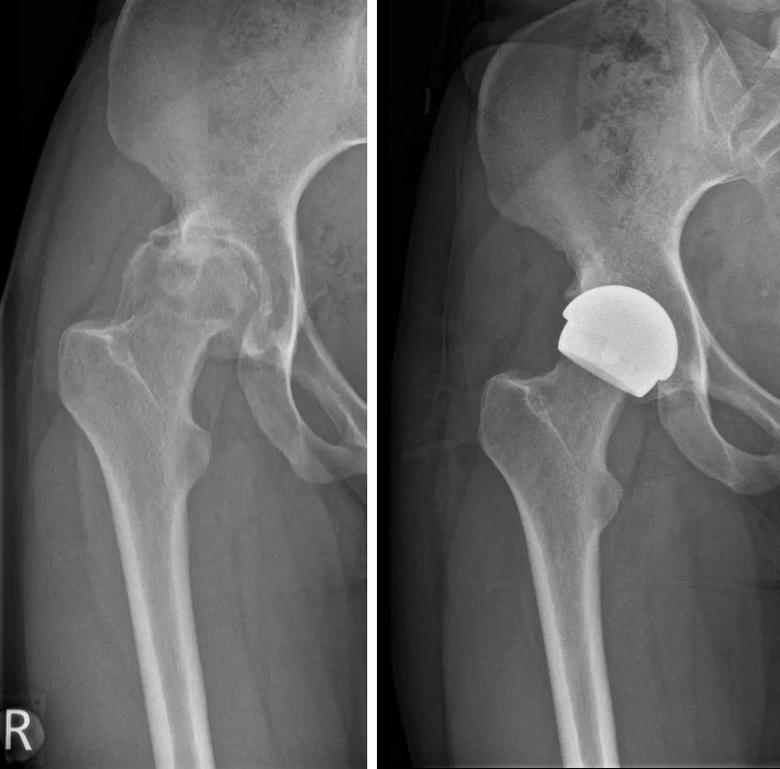

Imaging scans before and after hip resurfacing with the H1 implant

Imaging scans before and after hip resurfacing with the H1 implant.